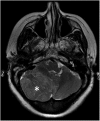

Hamartomas are tumours composed of mesenchymal tissues such as cartilage, fat, connective tissue and smooth muscle and can be found in virtually any organ system. These masses commonly develop sporadically, but are also seen in certain syndromes such as tuberous sclerosis or Carney triad. While their imaging appearance varies depending on the organ they arise from, findings are usually unique and a diagnosis can be confidently made. Radiologists must be aware of the clinical and imaging presentations of these lesions with the particular goal of avoiding unnecessary studies or invasive procedures. Furthermore, knowledge of common syndromic entities is crucial, as the radiologist may be the first to suggest the diagnosis.

- Saleem SN, Said AH, Lee DH. Lesions of the hypothalamus: MR imaging diagnostic features. Radiographics 2007; 27: 1087–108. doi: https://doi.org/10.1148/rg.274065123 - DOI - PubMed

- Glastonbury CM, Osborn AG, Salzman KL. Masses and malformations of the third ventricle: normal anatomic relationships and differential diagnoses. Radiographics 2011; 31: 1889–905. doi: https://doi.org/10.1148/rg.317115083 - DOI - PubMed